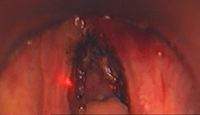

Intervention chirurgicale sous anesthésie générale: Laser CO2 (lumière rouge) des 2 cordes vocales pour myxœdème laryngé

Patient avec dysphonie (voix cassée): sous anesthésie générale par jet ventilation (tuyau sous les cordes vocales): découverte de lésion de la corde vocale gauche. Après biopsie de cette lésion, l'examen anatomo-pathologique révélera une tuberculose laryngée isolée et exclura l'hypothèse diagnostique de cancer (carcinome épidermoïde).